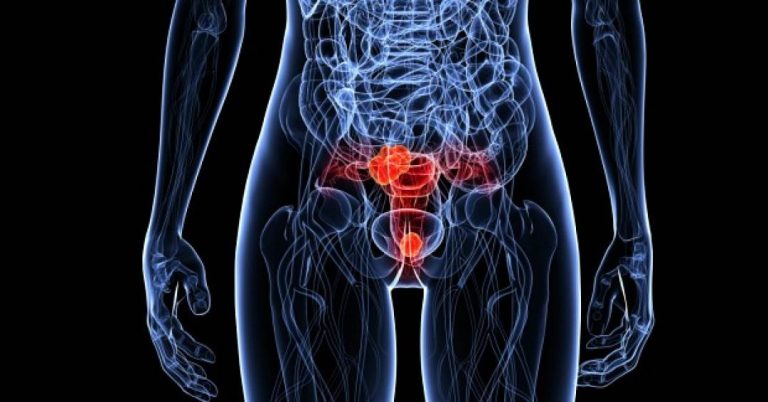

O câncer do colo de útero

Deflagrado pela infecção por certos tipos de papilomavírus (HPV), transmitidos sexualmente, o câncer do colo de útero é o terceiro mais comum entre mulheres. Também é o quarto tipo de tumor que mais mata pessoas com útero, principalmente as que vivem em situação de vulnerabilidade social, negras e com baixos níveis de escolaridade. Em pacientes que vivem com o HIV, a possibilidade de desenvolver o problema é até cinco vezes maior.